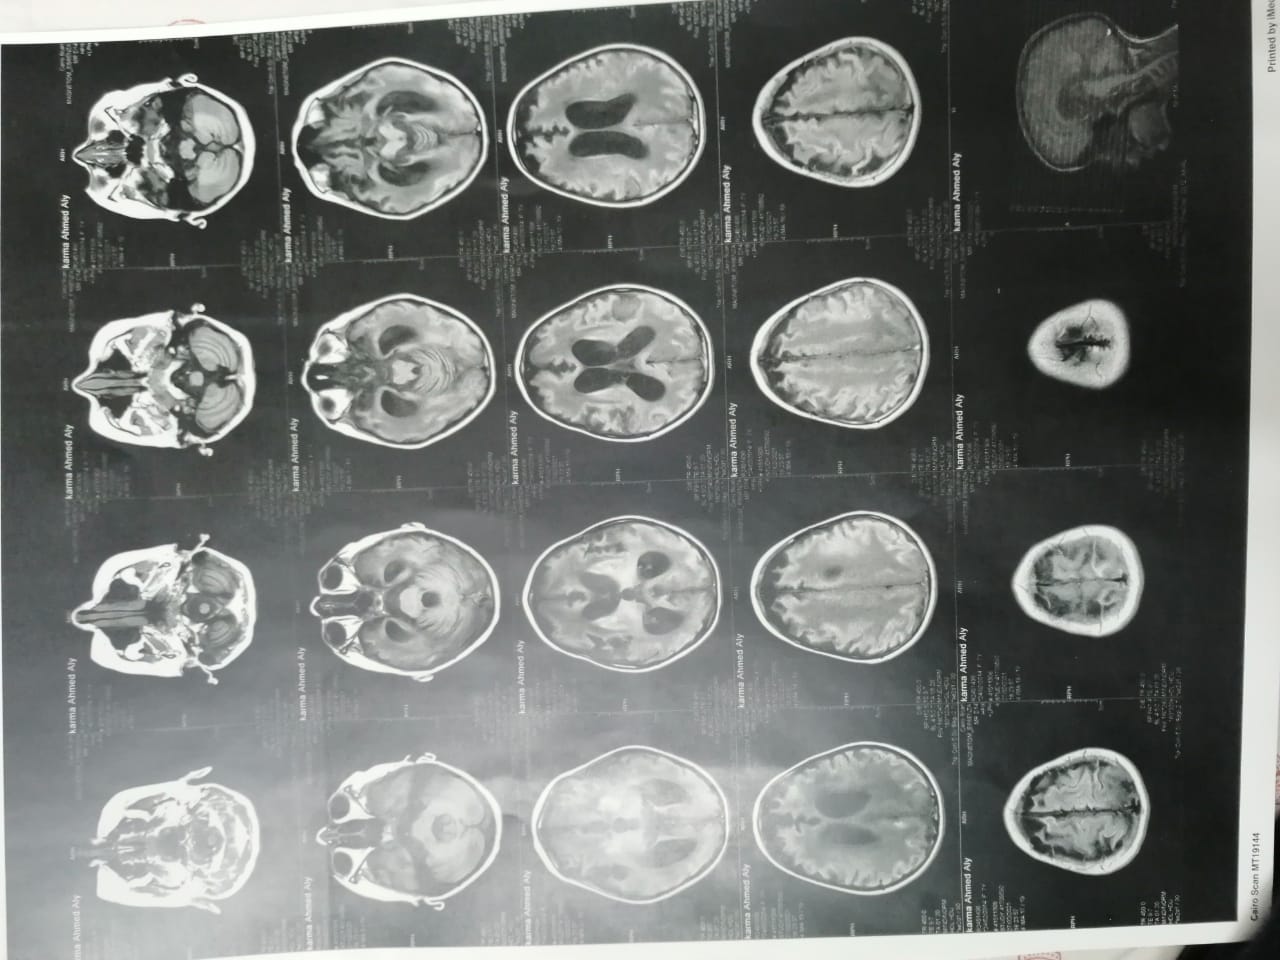

وأشار إلى أنه بعد خروج كارما من المستشفى تم إجراء فحوصات أخرى عليها، تبينت عدم التطابق بين التقارير الطبية لها بداخل المستشفى والفحوصات الجديدة.

وقال علي: "بنتي جالها ضمور في المخ وفي كل الحواس، بسبب الدوا الغلط، بنعملها علاج طبيعي بيتكلف في الشهر 20 ألف جنيه"، مشددًا": "هي بتفتح عينها بس".